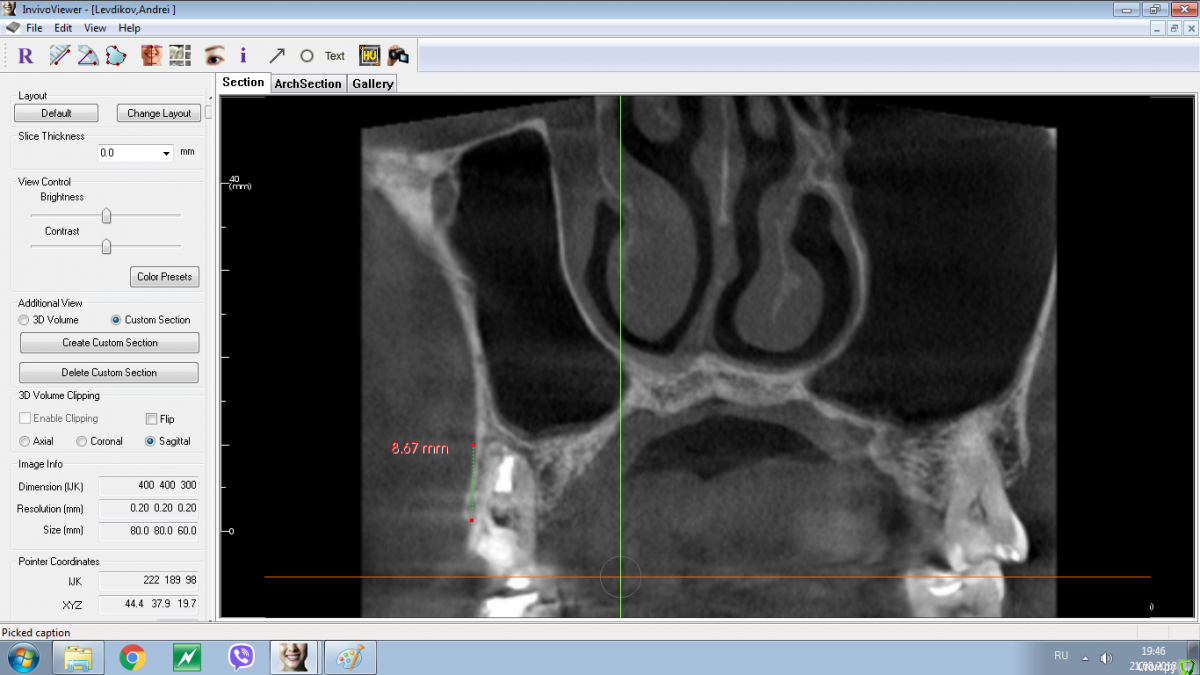

колесников Опубликовано 13 марта, 2019 Поделиться Опубликовано 13 марта, 2019 В первой лунке имплант ,второй корень подготовлен под удаление. Для консервации используйте графт это минимизирует атрофию кости,дефицит мягких тканей случится в любом случае,на момент имплантации понадобится сст. Ссылка на комментарий